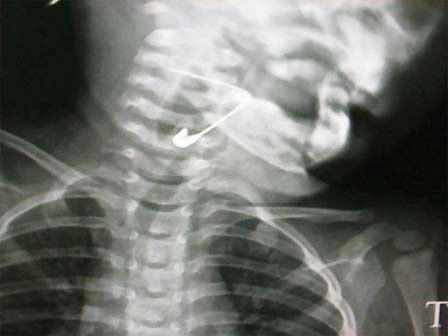

Gắp thành công kim băng dài hơn 3 cm trong thanh quản bé gái

Trong lúc chơi đùa, bé gái 18 tháng tuổi ở Quảng Nam vô tình nuốt chiếc kim băng vào cơ thể.